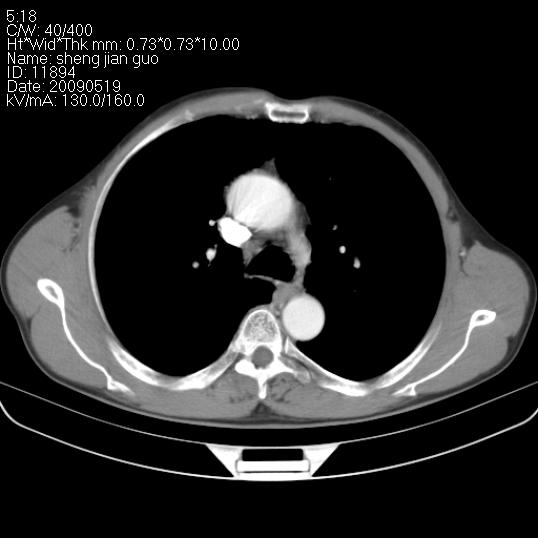

以下是引用zjzjr在2009-5-19 17:25:00的发言:[br]支持楼主考虑,另左肺下叶阻塞性炎症。

以下是引用zhao_bin2008在2009-5-19 17:48:00的发言:[br]支持左肺下叶周围型肺癌并阻塞性肺炎。

以下是引用zsl6918在2009-5-20 7:10:00的发言:[br]左侧中心型肺癌!